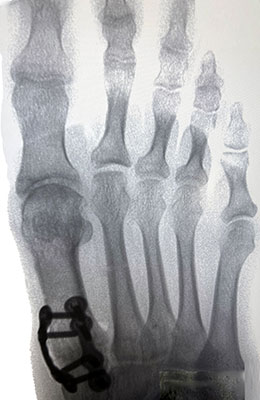

Before

Minimally Invasive Bunion Surgery featuring the CrossRoads miniBunion™ System before

After

Minimally Invasive Bunion Surgery featuring the CrossRoads miniBunion™ System after

Minimally Invasive Bunion Surgery featuring the CrossRoads miniBunion™ System

Eva is a 24-year-old female who had just began working at a job that required high fashion shoes. She was in constant pain but could not take time off work. Our miniBunion™ Minimally Invasive Bunionectomy allowed her to continue to work and be on her foot with full recovery and return to regular shoes by 6 weeks. She had an amazing range of motion, no more bunion pain, and absolutely no visible incision. After picture taken six weeks post-surgery.